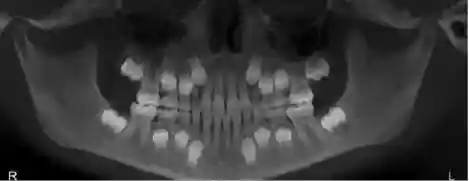

如果在这段时间,我们透过X光来观察颌骨内的情况,那么就会是这个样子的:

如果拨开皮肤和肌肉组织,再仔细地剥去颌骨表面骨皮质,那么就是这样的:

这张….略有Cult片的赶脚吧~~~